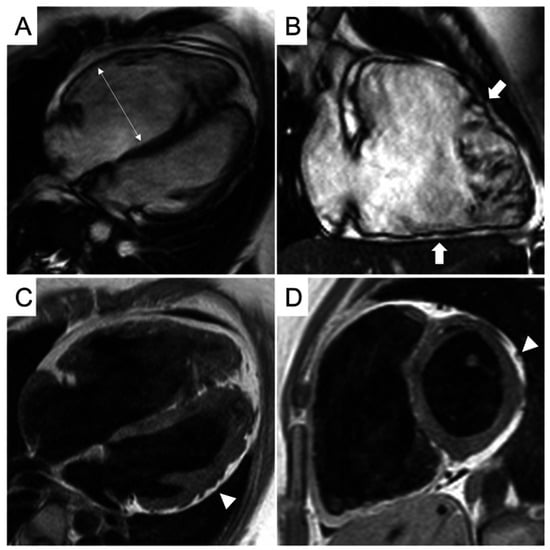

CMR findings and differentiating features are as follows (Figure 8):

Figure 8.

CMR frames of a patient with biventricular ACM. Morpho-functional abnormalities of the RV can be appreciated on a 4-chamber view (A) and right ventricular 2-chamber long-axis view (B) of cine images, evidencing RV dilatation (A, double-head arrow) and multiple sacculations of the inferior and RVOT regions (B, arrows). Structural alterations of the LV are showed in a 4-chamber view (C, arrowhead) and short-axis view (D, arrowhead) of T1-weighted images, where fibro-fatty infiltration of the infero-lateral LV walls becomes evident as a hyperintense signal with a typical bite-like pattern. ACM, arrhythmogenic cardiomyopathy; LV, left ventricle; RV, right ventricle; RVOT, right ventricle outflow tract. Reproduced from: Cipriani, A., et al. (2023) [39]. Licensed under CC BY 4.0 (https://creativecommons.org/licenses/by/4.0/ accessed on 15 December 2025).

- LGE Pattern: The LGE in ACM is typically subepicardial or mid-myocardial, with a predilection for the basal and mid-cavity segments of the LV inferolateral wall. This pattern significantly overlaps with viral myocarditis [39].

- RV Involvement: A key differentiator is concomitant RV structural abnormality. Findings include RV dilation, systolic dysfunction (reduced RV ejection fraction), and LGE or fat infiltration in the RV free wall. However, in left-dominant ACM, RV changes can be subtle or absent.

- Regional Wall Motion Abnormalities (RWMAs): Cine imaging may show regional hypokinesia or akinesia in the LV inferolateral wall or RV, which can also be seen in myocarditis.

Given the overlap, a family history of sudden cardiac death or ACM, and the presence of characteristic ECG findings (e.g., T-wave inversions in right precordial leads or inferior/lateral leads, albeit non-specific) are crucial clues. The 2023 ESC Cardiomyopathy guidelines emphasize that in cases of suspected myocarditis with an atypical or recurrent course, the diagnosis of ACM should be considered, and genetic testing for desmosomal mutations (e.g., PKP2, DSP, and DSG2) is recommended [42]. A pathogenic variant confirms the diagnosis and enables cascade screening of family members.